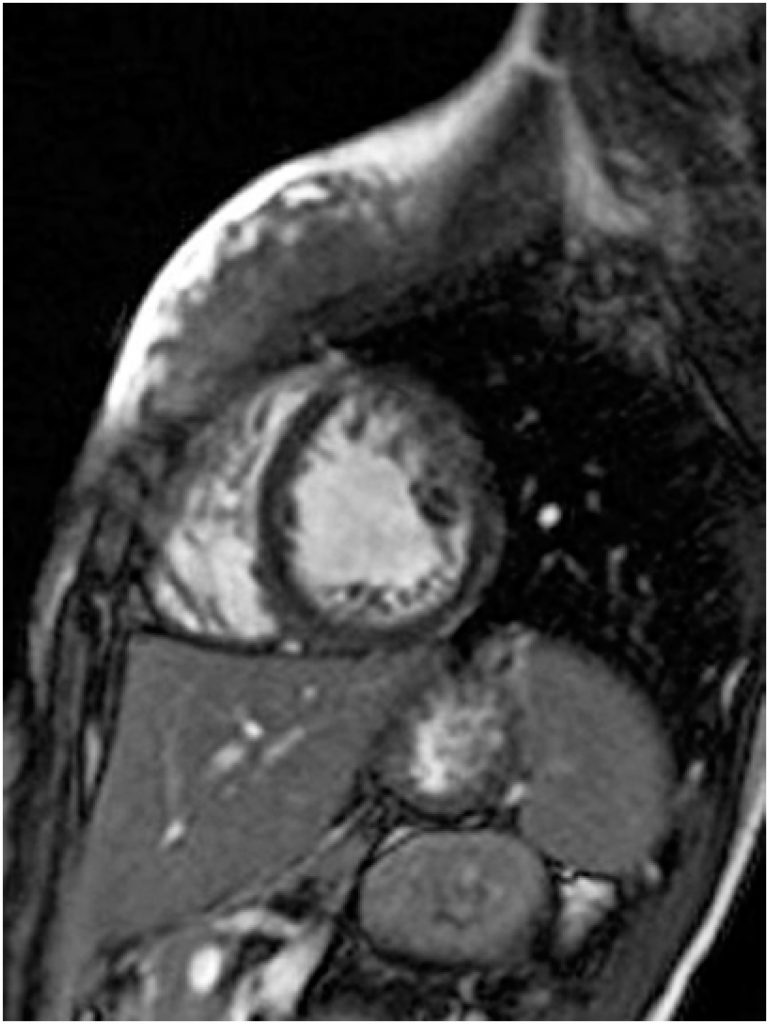

The left ventricular noncompaction is a congenital cardiomyopathy characterized by the presence of abnormal trabeculations in the left ventricle. The present study describes the case of a 14-year-old female Para athlete, who plays goalball. She was asymptomatic, with history of congenital nystagmus and mild visual impairment, who presented nonspecific electrocardiographic abnormalities during pre-competition screening. Cardiac magnetic resonance imaging showed left ventricular non-compaction (non-compacted to compacted layer ratio equal to 2.5) and mild biventricular systolic dysfunction. Initially, the patient was excluded from sports participation and clinical follow-up was performed every three months. Patient remained asymptomatic during the one-year follow-up, with no history of unexplained syncope, marked impairment of systolic function or significant ventricular arrhythmias at the exercise stress test. Finally, she was released for competitive goalball participation and clinical follow-up was continued every 6 months. There is no consensus regarding the eligibility criteria for sports participation in cases of left ventricular non-compaction. Thus, it is prudent to individualize the decision regarding practice of sports, as well as to consider participation in competitive sports for asymptomatic individuals and with no disease repercussions.